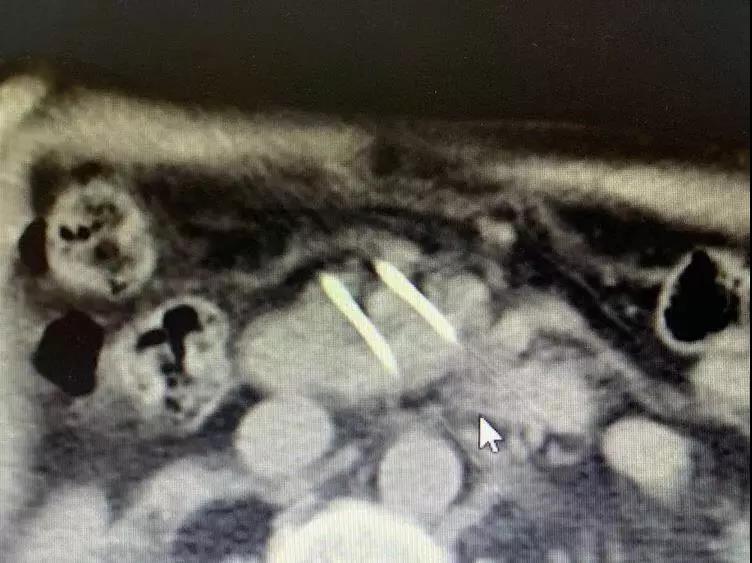

手术中

胰腺肿瘤不可逆电穿孔术

为了早一点治疗父亲的疾病,梭的儿子急忙的带着他在8月31号来到复大肿瘤医院。经过多次详细检查,诊断为:胰腺癌钩突部腺癌III期和2型糖尿病。肝、肺、甲状腺等多处出现结节,需要随后跟进治疗;牛立志博士与多名医生针对梭的病情展开讨论以及跟家属沟通后,分别在9月6号行“锁骨下静脉置管术”;9月7号行“胰腺肿瘤不可逆电穿孔术”。术后经过一系列的护理,梭的情况逐渐转好。